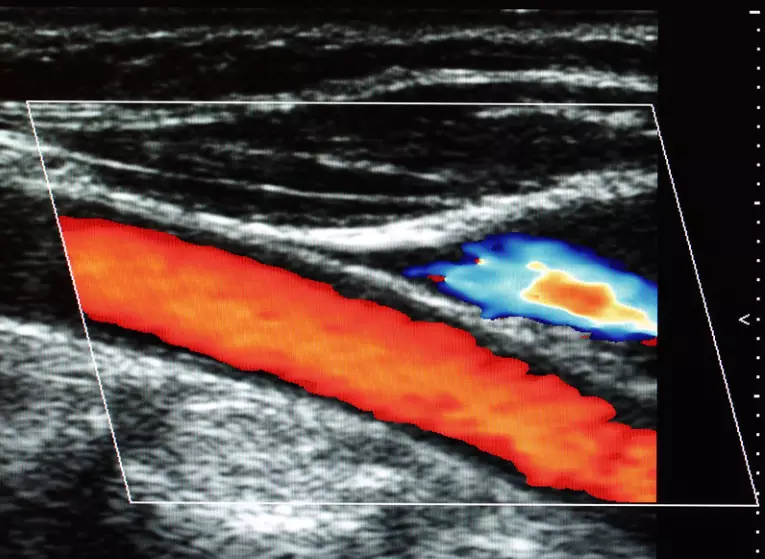

Echo: halsslagaders (duplex)

Een echo van de halsslagaders is een pijnloos onderzoek waarmee de bloedvaten in de nek zichtbaar worden gemaakt met behulp van geluidsgolven. De cardioloog kan hiermee beoordelen of er vernauwingen, plaques of andere afwijkingen aanwezig zijn die de bloedstroom naar de hersenen kunnen beïnvloeden. Tijdens het onderzoek beweegt de laborant een klein apparaatje over de huid, terwijl beelden in realtime op een monitor verschijnen. Het onderzoek duurt meestal slechts enkele minuten en geeft waardevolle informatie over het risico op beroertes en hart- en vaatziekten.